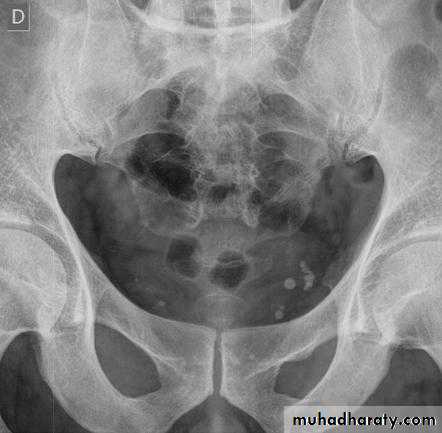

Abdominal calcifications

Assessment of the shape and pattern of abdominal calcification will usually limit the diagnosis to one or two choices. Calcification in the abdomen are likely to be :1. Pelvic vein phleboliths: very common, may be mistaken for urinary stones & fecoliths

4. Uterine fibroids: irregular shaped well-defined calcifications conforming to the spherical outline of fibroids